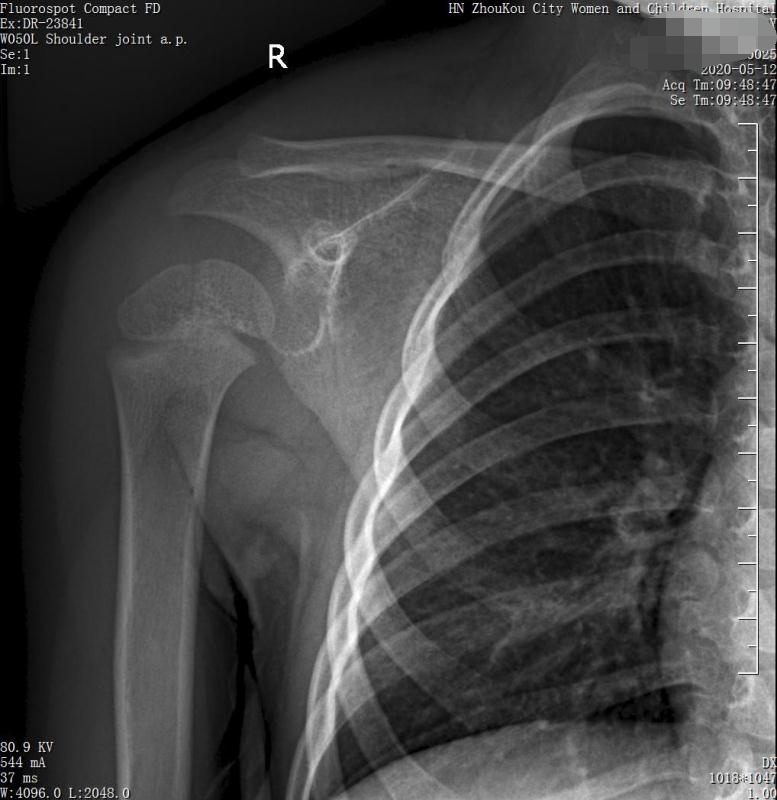

3岁女童以突发右侧肩胛部肿物来院检查,病人无发热、感冒症状,拍右肩关节正位片示:右侧肩关节肩胛岗上缘骨质密度欠均匀,建议CT进一步检查。

通过CT平扫发现:右侧肩胛骨骨质密度不均,骨质内可见“虫食样”低密度影,骨质边缘可见多发放射状骨针,呈“日光射线征”。周围软组织明显肿胀,肌间隙模糊。CT检查意见:考虑:右肩胛骨占位,骨肉瘤可能,不除外其它恶性肿瘤病变,请结合临床及相关检查注意复查。 影像鉴别诊断:骨肉瘤是指起源于骨间叶组织,遗留形成骨细胞直接形成骨样组织为特征的恶性肿瘤,是比较常见的骨恶性肿瘤,好发于十到二十岁青少年,骨肉瘤常见于管状骨,股骨远端胫骨近端最多见,表现为疼痛局部肿胀运动障碍,实验室检查都有碱性磷酸酶升高。